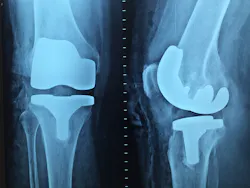

Regent Surgical Health announced a partnership with physician partners from the Center for Specialized Surgery and Lee Health. The Center for Specialized Surgery specializes in orthopedic surgeries, including foot and ankle, sports medicine, total joint replacement, spine surgery, pain management, and hand, wrist and elbow surgeries.